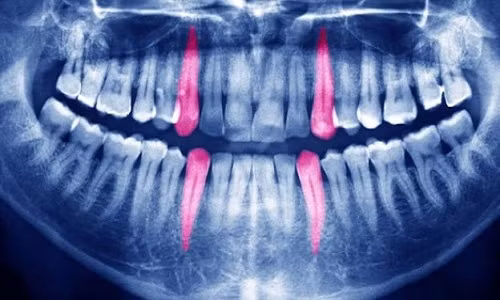

| Kim loại dùng để hàn răng có thể làm tăng lượng khí hydro trong răng, khiến răng phát nổ. Ảnh: Alamy. |

Có lẽ, câu trả lời phù hợp nhất đến từ hóa chất con người dùng để hàn răng. Trước khi thủy ngân được sử dụng vào năm 1830, những chất khác như chì, thiếc, bạc và các hợp kim từng được dùng để hàn răng. Andrea Sella, giáo sư Hóa vô cơ tại Đại học London, Anh, chỉ ra nếu hai kim loại khác nhau được sử dụng để hàn răng, chúng sẽ tạo ra một kiểu pin điện hóa. Toàn bộ miệng sẽ biến thành một bộ pin điện áp thấp vì các hỗn hợp kim loại trong miệng có thể tự phát điện. Điều này làm tăng khả năng tích tụ khí hydro trong răng.

Một chiếc răng suy yếu có thể phát nổ dưới áp lực này. Thậm chí, khí hydro có thể phát nổ nếu bị đốt cháy trong khi bệnh nhân hút thuốc hoặc kim loại trong miệng phát ra tia lửa. Tuy nhiên, các bệnh nhân có răng phát nổ chưa từng hàn răng nên giả thuyết này không chính xác. Hiện nay, nguyên nhân của các vụ nổ răng vẫn còn là bí ẩn.